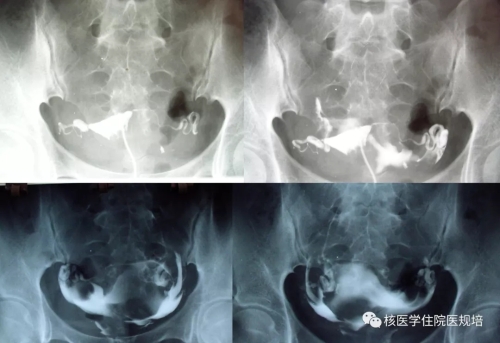

子宫输卵管造影(HSG)检查:经宫颈口注入造影剂顺利,宫腔形态大致正常,双侧输卵管走行可,通畅,盆腔内造影剂弥散良好。检查结论:子宫输卵管造影未见明显异常(图1)。

图1 子宫输卵管造影(HSG)检查